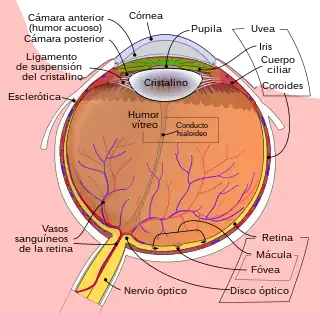

Dibujo esquemático del ojo humano. | ||

La estructura y el funcionamiento del ojo es muy similar en la mayoría de los vertebrados. El globo ocular es básicamente una esfera llena de un líquido transparente, llamado humor acuoso, que está compuesto por un 99 por ciento de agua. La pared está formada por 3 capas: la más interna o retina, la intermedia o coroides, y la más externa, que se llama esclerótica.

Posee una lente llamada cristalino, que es ajustable según la distancia; un diafragma, que se llama pupila (cuyo diámetro está regulado por el iris), y un tejido sensible a la luz, que es la retina.

Con la excepción de los peces, anfibios y ofidios, el enfoque se consigue gracias al cambio de forma del cristalino mediante un músculo llamado músculo ciliar.

La luz penetra a través de la pupila, atraviesa el cristalino y se proyecta sobre la retina, donde se transforma, gracias a unas células llamadas fotorreceptoras, en impulsos nerviosos, que son trasladados, a través del nervio óptico, hasta el cerebro.

Los ojos de todos los vertebrados comparten un modelo de circuito retiniano común: cinco clases de neuronas, dispuestas en tres capas nucleares que flanquean dos capas sinápticas.[10]

Los músculos extrínsecos del globo ocular son los mismos en todos los vertebrados, incluido el hombre.[11]